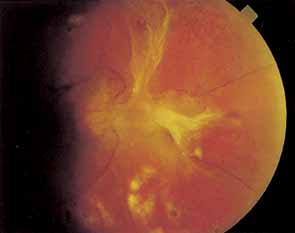

Panretinal Photocoagulation

When well-focused, intense light is absorbed by pigmented cells (such as erythrocytes or pigment epithelial cells), it is converted to heat, coagulating the cells and surrounding tissues. The first photocoagulator, the xenon arc, produced an intense light that was successful in obliterating neovascularization that was either on the surface of the retina or only slightly elevated (Fig. 19). Clinicians thought that eyes treated with xenon arc photocoagulation had good regression of retinopathy and fewer vitreous hemorrhages than would have been expected had they not been treated. However, xenon arc photocoagulation had severe limitations. First, the heat generated was often insufficient to obliterate highly elevated neovascularization. Second, neovascularization arising from the optic nerve could not be directly treated because the intense light beam damaged the optic nerve. Finally, in many cases, all of the neovascularization was initially obliterated, but new areas of neovascularization later developed. For these reasons, the long-term results of photocoagulation were considered by many observers to be no better than no treatment at all.

Fig. 19 A. Neovascularization immediately after xenon-arc photocoagulation. B. One year later. The neovascularization elsewhere (NVE) has been obliterated.

To prevent new areas of neovascularization, several ophthalmologists began to photocoagulate not only neovascularization but all intraretinal hemorrhages as well (“shoot the red”), on the grounds that they represented areas of hypoxia that could later develop into proliferative retinopathy. They soon noted that the cases that had the most intraretinal hemorrhages and therefore received the most initial photocoagulation frequently had the best long-term results, with permanent regression of neovascularization (Fig. 20). In such cases, the optic disc often became pale, indicating optic atrophy.

Fig. 20 A. Neovascularization of the disc (NVD) and a small vitreous hemorrhage. Panretinal photocoagulation was given. B. Two months later, the NVD has completely regressed.